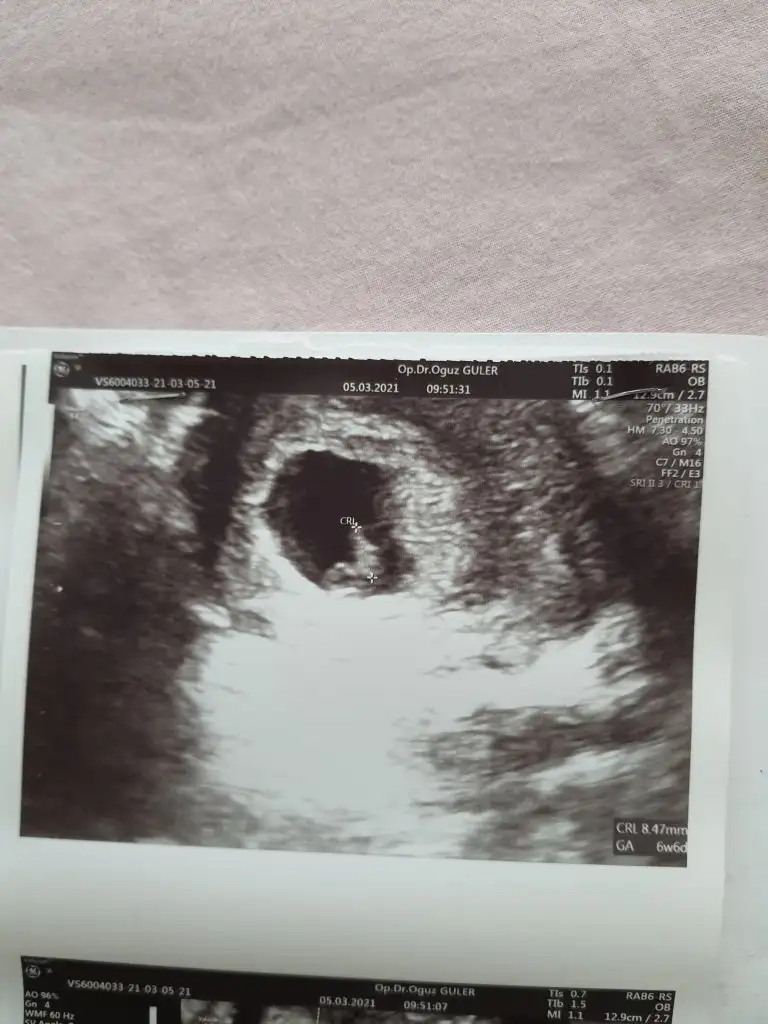

Merhaba 7 hafta 5 günlük burada karından ultrasom abdominal cinsiyet tahmini alabilir miyim bende şimdiden teşekkür ederim.